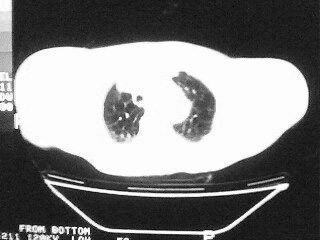

女,79,咳 嗽月余,无其它不适

后纵隔内左心房至肝左叶后方椎体中线偏左巨大软组织包块,其壁均匀比较薄,其内可见宽气液平。

考虑食管裂孔疝。建议钡餐检查